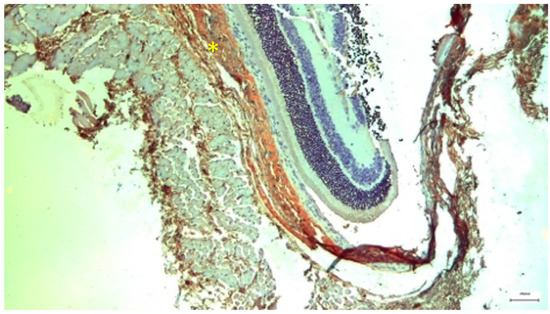

Background/Objectives: Cisplatin is a potent chemotherapeutic agent whose clinical utility is limited by severe side effects, including neurotoxicity affecting the ocular system. The pathophysiology involves oxidative stress and mitochondrial dysfunction, to which the retina is particularly vulnerable. Selenium (Se), an essential trace element and component of antioxidant enzymes, has shown potential in mitigating cisplatin toxicity, although its efficacy with respect to retinal structure and the influence of administration routes remain underexplored. This study aimed to evaluate the protective efficacy of selenium against cisplatin-induced retinal toxicity and compare the effects of intraperitoneal and oral selenium administration. Methods: Forty adult male Wistar rats were randomized into four groups (n = 10 each): Group A (Cisplatin Monotherapy, 3.5 mg/kg IP for 5 days; cumulative dose 17.5 mg/kg); Group B (Cisplatin + Intraperitoneal Selenium, 2.73 mg/kg; cumulative dose 60 mg/kg); Group C (Control); and Group D (Cisplatin + Oral Selenium). Selenium prophylaxis, administered as sodium selenite (Na2SeO3), began two days prior to cisplatin administration and continued for 15 days post-treatment. Retinal evaluation two weeks after cisplatin cessation included light microscopy, semi-quantitative immunohistochemical (IHC) analysis for inflammatory (IL-6) and fibrotic (TGF-β2) markers, and Transmission Electron Microscopy (TEM) for ultrastructural analysis, which were the primary endpoints. Statistical differences in the IHC scores were analyzed via the Kruskal‒Wallis H test with Dunn’s post hoc comparisons. Results: Cisplatin monotherapy (Group A) caused severe disruption of the retinal architecture, including edema, reactive gliosis, and significant upregulation of IL-6 and TGF-β2. Ultrastructural analysis revealed mitochondrial swelling (cristolysis) and photoreceptor disk fragmentation. Intraperitoneal selenium (Group B) was associated with significant structural preservation and intact mitochondria, with TGF-β2 levels comparable to those of the controls, although the IL-6 level remained moderately elevated. Conversely, oral selenium (Group D) suppressed both IL-6 and TGF-β2 expression to near-negative levels but provided less ultrastructural protection, resulting in persistent mitochondrial swelling and focal photoreceptor disruption. Conclusions: Systemic cisplatin induces severe subcellular retinal toxicity characterized by mitochondrial damage and photoreceptor degeneration. Selenium supplementation attenuates these effects; however, outcome patterns differ by administration route. Intraperitoneal selenium was associated with greater morphological and ultrastructural preservation despite persistent IL-6 elevation, whereas oral selenium normalized immunohistochemical marker expression to near-control levels but was associated with more pronounced residual subcellular damage on qualitative TEM assessment. These preliminary morphological and immunohistochemical findings suggest that the route of selenium delivery may influence its neuroprotective profile; however, pharmacokinetic measurements and functional retinal assessments, such as electroretinography, are warranted before its clinical translation. Full article